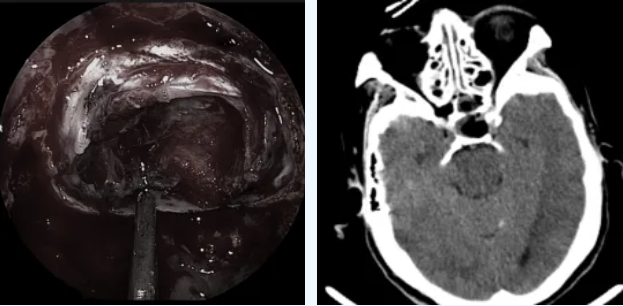

医生使用直径仅4毫米的高清神经内镜,通过鼻孔进入,手术过程清晰地显示在高清屏幕上。肿瘤被精准完整切除,完好保护了周围的神经、血管等重要结构。

肿瘤全切,术后CT未见出血

术后第二天,李奶奶就能下地行走。复查显示她的生长激素水平已降至0.931ng/mL,恢复正常范围。